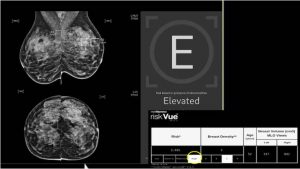

乳房X光检查用于早期发现乳腺癌,以便更轻松地进行管理和治疗。瑞典一项大型试验发现,当放射科医生使用人工智能辅助阅片时,乳腺癌的检出率有所提高,从而减少了侵袭性和晚期病例的发生。

这项研究发表在周四出版的医学期刊《柳叶刀》上,研究对象为超过10万名接受乳房X光检查的女性。其中一半女性的检查由人工智能辅助完成,另一半女性的乳房X光片则由两位不同的放射科医生进行阅片,这在欧洲大部分地区是一种被称为“双重阅片”的标准做法。但在加拿大,通常由一位放射科医生阅片,并不采用这种做法。

在为期两年的研究中,人工智能辅助的乳腺X光检查结果被分为两组。低风险病例只需一名放射科医生检查,而高风险病例则需要两名放射科医生检查。